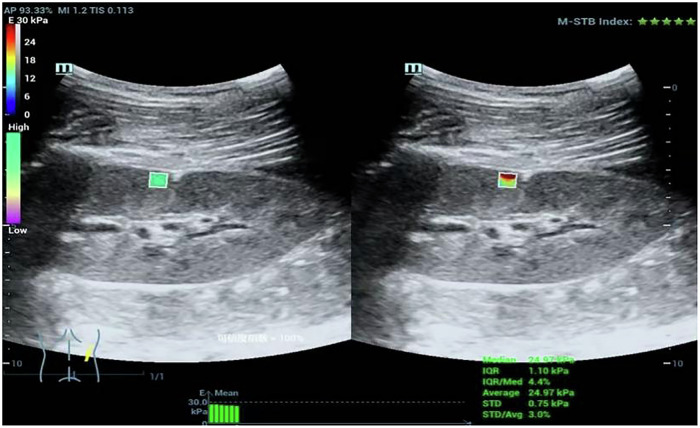

Materials and methods: We used a cross-sectional design involving 76 pediatric patients with PNS and a control group, and measured renal stiffness through SWE The clinical characteristics of the nephrotic group were collected, including age, sex, disease duration, clinical type, 24-h urine protein, plasma albumin, and the relationship with 2D-SWE value was analyzed.

Results: Our results demonstrated a significant difference in renal elasticity, with the nephrotic syndrome group exhibiting a mean shear wave velocity (YM) of 22.36 ± 8.53 kPa compared to 17.51 ± 4.09 kPa in controls (p < 0.05). Furthermore, the area under the ROC curve for SWE was 0.67, indicating moderate predictive capability for renal damage. Notably, there were no significant differences in YM values across various clinical classifications of nephrotic syndrome, suggesting a uniform renal damage assessment irrespective of clinical type. Additionally, renal elasticity did not significantly vary regardless of whether the patient's proteinuria had improved. (p = 0.464), indicating SWE's potential as an independent biomarker.